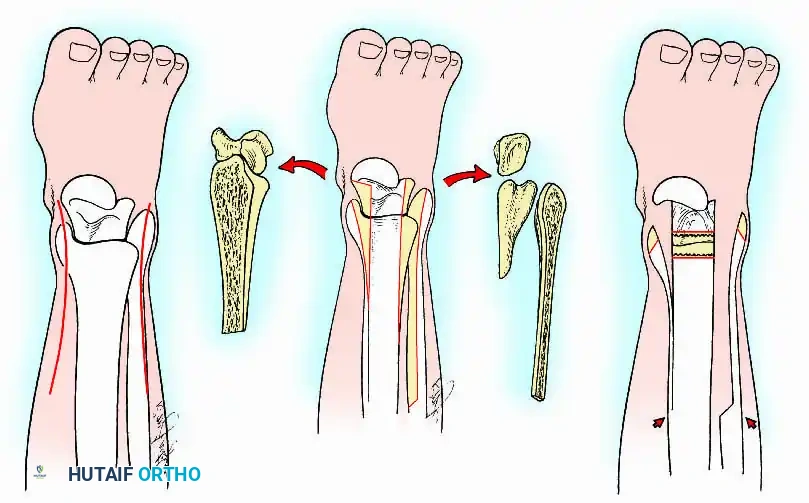

Transmalleolar (Transfibular) Approach

This approach utilizes a lateral incision over the distal fibula. A transfibular osteotomy is performed, reflecting the distal fibula distally or excising it entirely to be used as autograft. This provides unparalleled exposure of the lateral half of the joint and the posterior facet. It is highly effective for correcting severe varus/valgus deformities. A supplementary medial incision (medial malleolar osteotomy) can be added for complete joint exposure.

- Contour Preservation (Fishscaling): The remaining articular cartilage is meticulously denuded using curettes, and the subchondral bone is "fishscaled" or aggressively petalled with a sharp osteotome. This preserves the native ball-and-socket contour of the ankle, maximizing inherent bony stability and minimizing limb shortening.

- Planar Resection (Parallel Cuts): Two parallel cuts are made—one through the distal tibial plafond and one through the talar dome—using an oscillating saw. This technique resects a minimal amount of bone but creates perfectly flat, highly vascular cancellous surfaces that allow for excellent apposition and easy posterior translation of the talus. Extramedullary alignment guides (often repurposed from total knee arthroplasty systems) can be utilized to ensure precise, parallel resections.